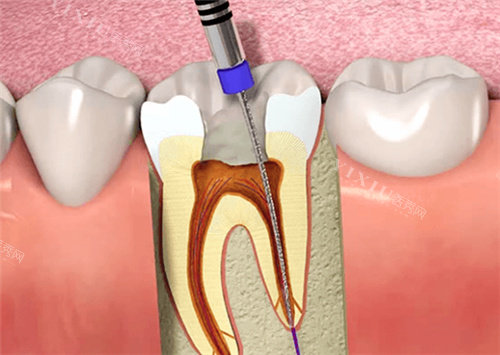

根据查询结果显示,高娅口腔确实具备合法执业资质,诊所登记类别为口腔专科门诊部,执业范围包括牙体牙髓病、牙周病、口腔修复等常规诊疗项目。

高娅医生:诊所研究人,毕业于重庆医学大学口腔医学校,从事口腔临床工作15年,擅长种植牙和美学修复。

种植牙:8000-15000元/颗